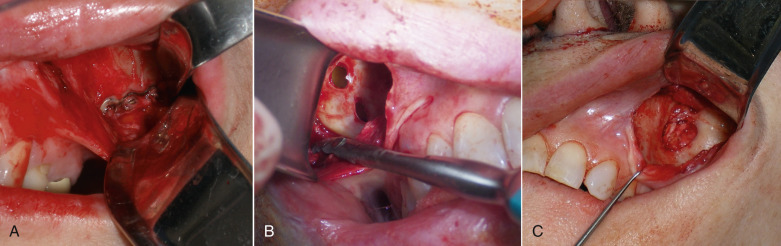

During preoperative evaluation, it is also important to evaluate the patient’s oral health. Placing implants in the presence of dental or periodontal disease can severely compromise the case and result in infection ( Fig. 7.6 ). Patients with oral disease must be treated to achieve a normal state of oral health prior to implant placement. All implant patients require a panoramic radiograph or computed tomography (CT) scan to rule out any osseous or dental or sinus pathology.

A 1-cm horizontal incision is made approximately 10–15 mm above the canine tooth. Using a radiowave or electrosurgery microneedle to incise the mucosa and soft tissues is hemostatic, and the incision is carried to the periosteal level of the canine fossa region ( Fig. 7.9 ). Alternatively, a vertical mucosal incision can be used but this approach provides less visual and working access compared with a horizontal entry. It is very common to see bleeding from the vascular rich mucosa and this is immediately cauterized with a small bipolar forceps to prevent bleeding throughout the case ( Fig. 7.10 ). The oral mucosa is very pliable, and even with a small incision, the surgical site can be well visualized when retracted. The incision continues to the periosteum and the entire dissection must remain subperiosteal. A Molt No.9 periosteal elevator is used to begin the subperiosteal dissection.